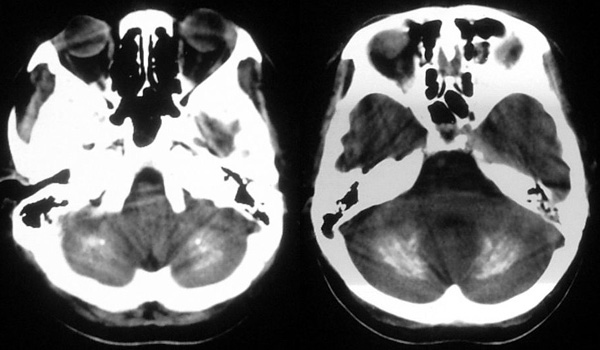

患者,女,49岁,头痛数年,有癫痫病史,无外伤史。

甲状旁腺低下:颅脑 ct 可见以基底节为中心的双侧对称性、多发性、多形性脑钙化的特点。除苍白球外,可广泛分布于壳核、尾状核、小脑齿状核、丘核、内囊及脑皮质、白质等处。